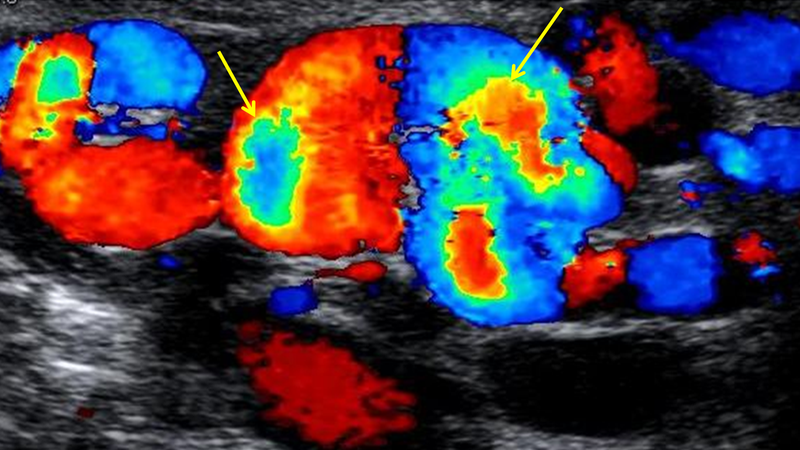

Trong số các phương pháp không xâm lấn, siêu âm Doppler màu được cho là phương tiện chẩn đoán hình ảnh tốt nhất. Việc đánh giá tình trạng giãn tĩnh mạch thừng tinh được đánh giá cả khi bệnh nhân ở tư thế nằm, tư thế đứng và khi thực hiện nghiệm pháp Valsava.

Theo Sarteschi và cộng sự, giãn tĩnh mạch thừng tinh có thể được chia ra thành 5 phân độ dựa trên tính chất dòng máu chảy ngược, chiều dài và sự thay đổi khi làm nghiệm pháp Valsava: